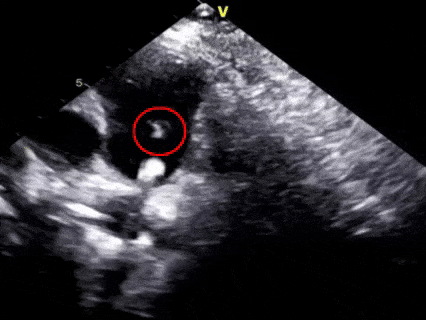

一“贴”,左盘贴壁

超声下可见左盘面展开

后撤整体系统,使左盘面贴靠肺动脉一侧